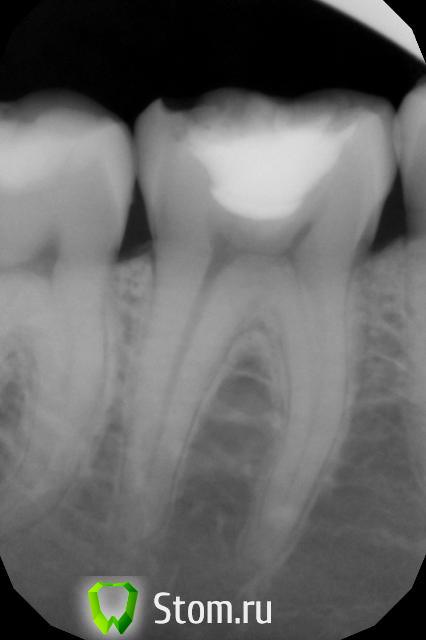

kurt Опубликовано 14 марта, 2012 Автор Поделиться Опубликовано 14 марта, 2012 снимок: Ссылка на комментарий

Magdalena Опубликовано 15 марта, 2012 Поделиться Опубликовано 15 марта, 2012 На мой взгляд, пломба стоит достаточно герметично. Как правило, такая "поверхностная" чувствительность может быть связана с избыточным сошлифованием эмали, как я и писала. Иногда причина может быть в погрешностях протокола постановки пломбы, лучше обратиться к лечащему врачу. Ссылка на комментарий